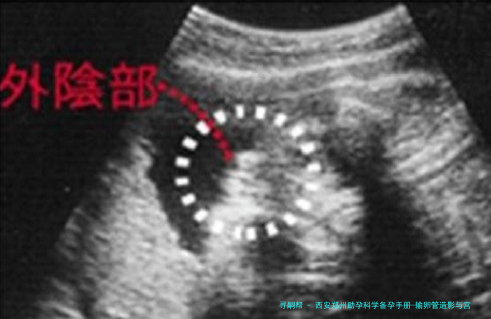

输卵管造影是一种评介输卵管通顺度的影像学检查。它并非将器械深入宫腔,而是通过宫颈向子宫腔体内注入造影剂,然后利用X光或超声技术,即时察看造影剂是否能够顺利通过输卵管并扩散至盆腔,进而评价输卵管是否通畅、阻塞的部位以及子宫腔的样子。

主要目的:其主要功能是诊断输卵管是否通畅,以及是不是存留堵塞、积水或粘连等等问题。它是不育症病因筛查中的重要一环,尤其适合于怀疑因输卵管因素导致不孕的女性。

结果呈现宫腔内真实影像,可活检输卵管显影情况,判断通畅、阻塞或积水